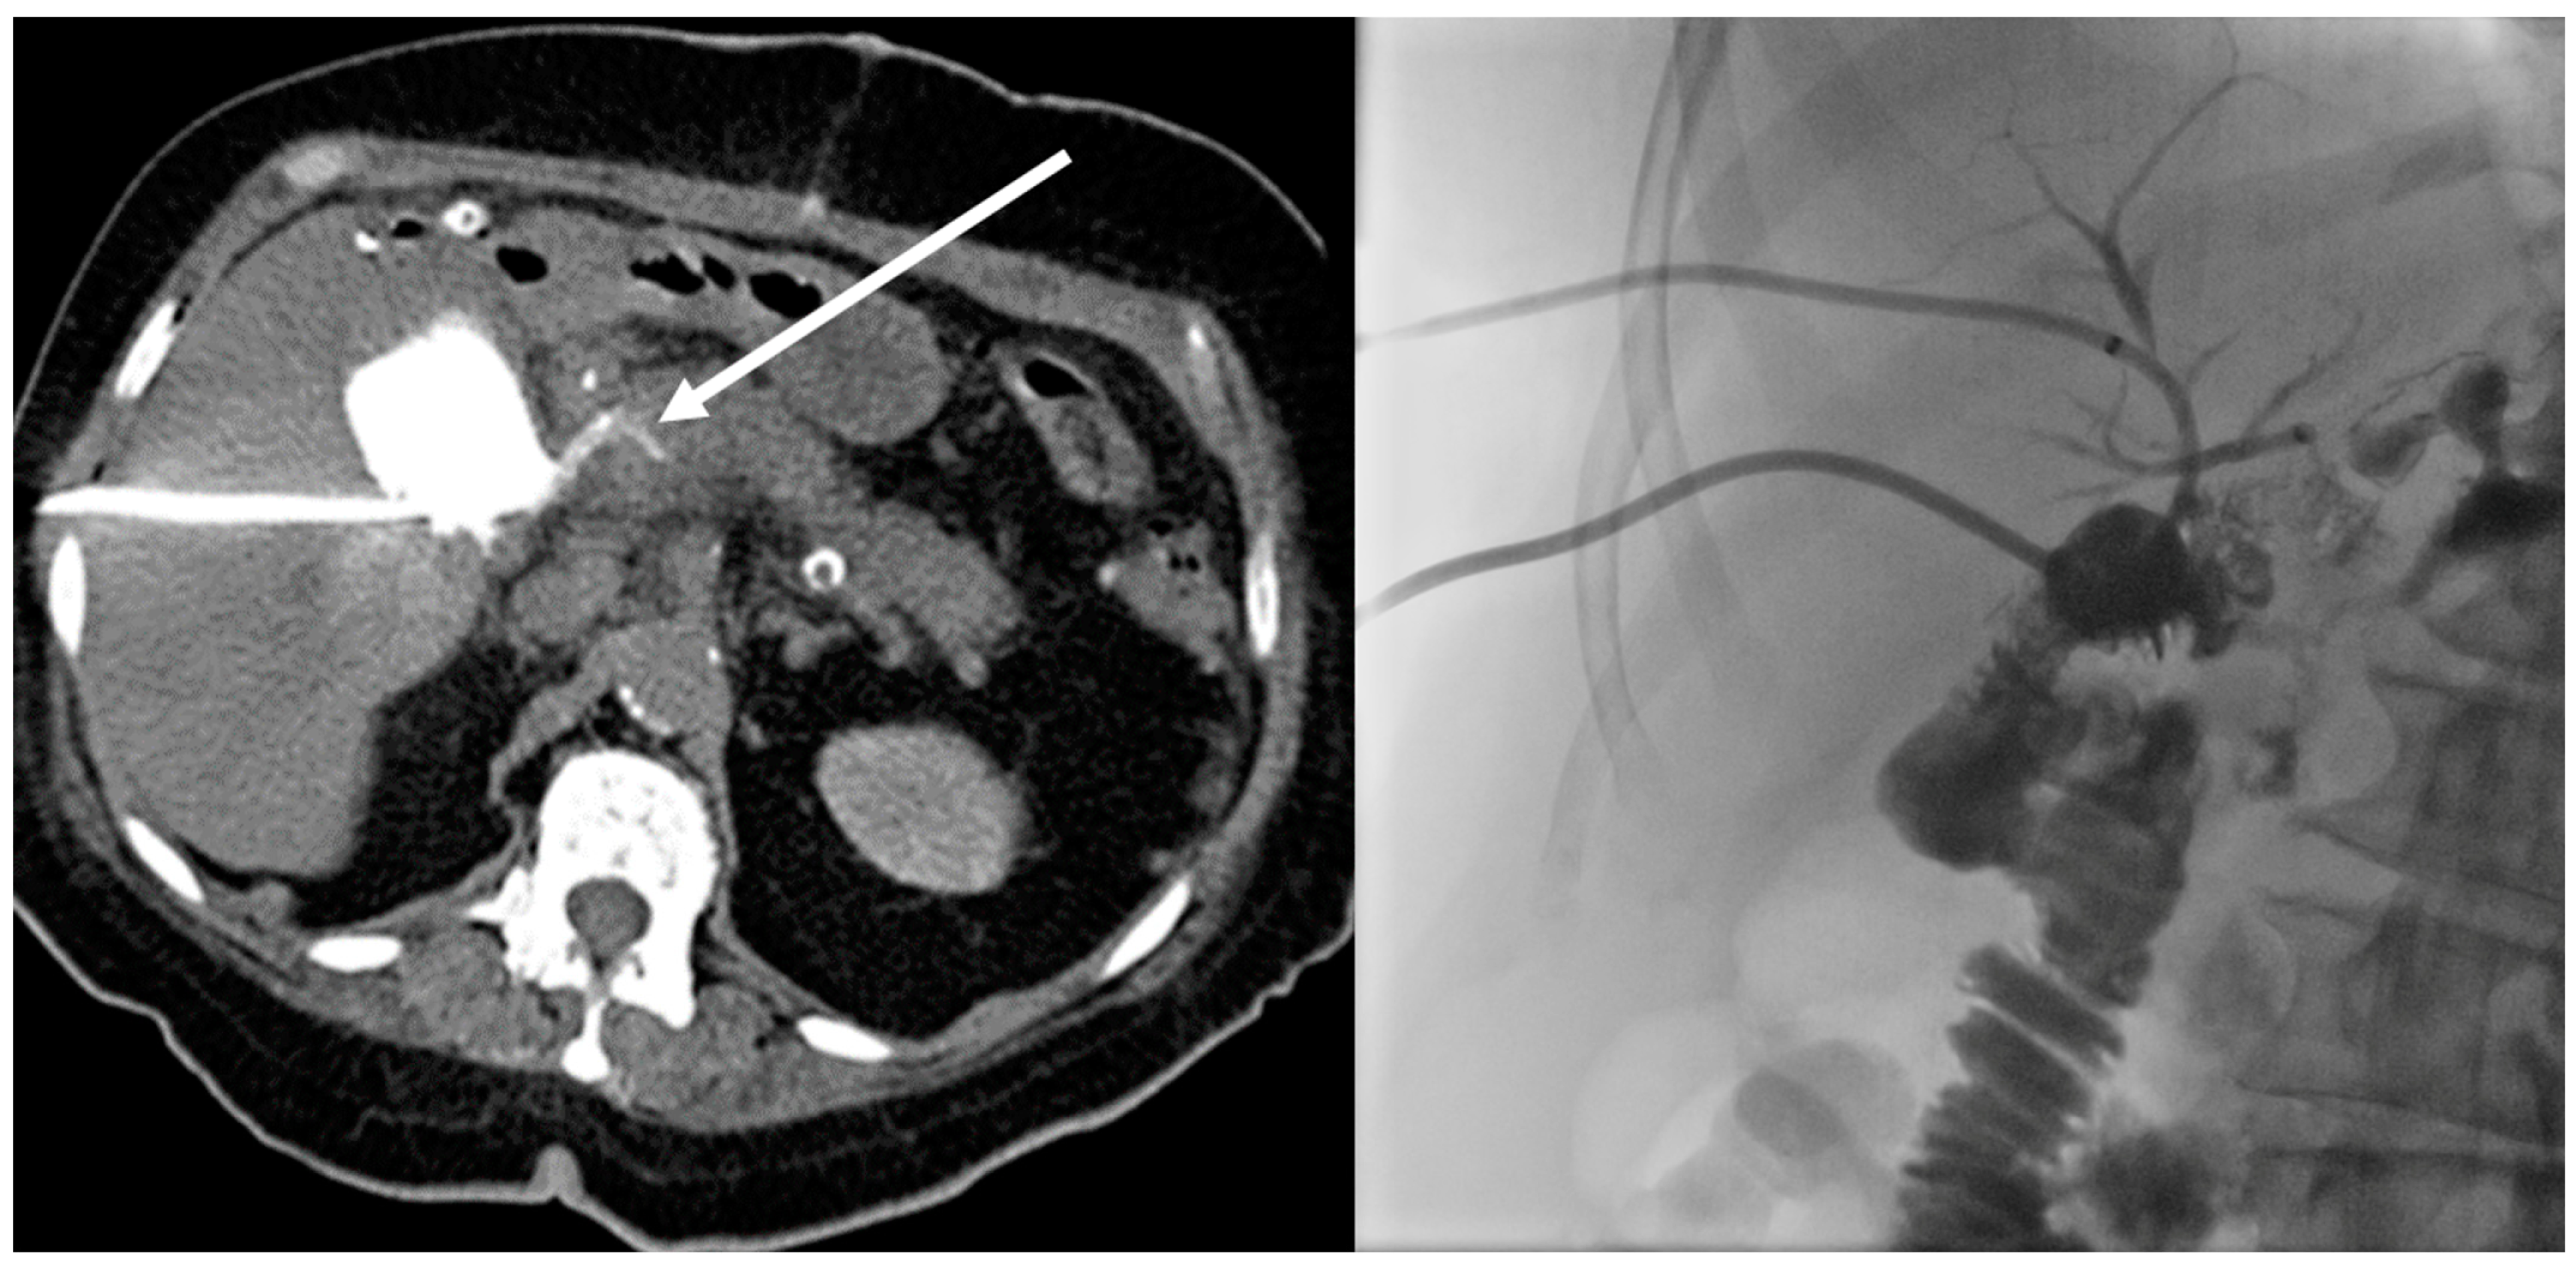

| Fistulas | 22 | 11 | 11 |

| Bile leaks | 13 | 8 | 5 |

| Insufficiencies after surgery | 12 | 12 | n/a |

| PTBD/ERCP | 9 |

| Surgery (revision) | 3 |

| Change of antibiosis | 3 |

| Endoscopic procedure | 2 |

| Repositioning of drainage | 2 |